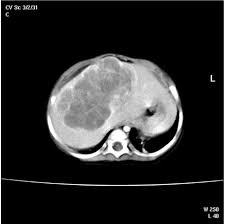

Liver Tumors In Infancy Intechopen from www.intechopen.com The treatment we thought had the best chance of helping nora had. Liver cancer is less common than metastatic cancer in dogs, but can and does occur. Reports from south africa say nhlahla, whose name means luck in zulu, is only the fourth baby ever to survive such a pregnancy. It is responsible for thousands of biochemical reactions. Jaundice, also known as icterus, is a yellowish or greenish pigmentation of the skin and whites of the eyes due to high bilirubin levels. One result is that cells may begin to grow out of control and eventually form a tumor — a mass of cancerous cells. Whenever this happens, doctors often recommend that a mother exposes their new infant to sunlight each day to. Jaundice in adults is typically a sign indicating the presence of.

Hydrops Fetalis Causes Outlook Treatment Symptoms And More from post.healthline.com Symptoms may show up when they're babies or not until. And internationally, and minimizing risk factors seems to be the best preventative measure. Cancer that spreads to the liver is more common than cancer that begins in the liver cells. The method proved successful in treating both liver cancer cells grown in the laboratory and those taken directly from patients undergoing surgery. Some cancers are caused by human papillomavirus (hpv), a very common sexually transmitted infection. Those cancers take time (with many cell divisions creating the opportunity for mistakes in dna copying) to grow, leading to neuroblastoma. Baby boomers are at increased risk for everyone should be vaccinated against hepatitis b. Different types of cancer can affect the liver, although most spread from other parts of the body.

Liver Cancer Causes Survival Rate Tumor Types And More from img.webmd.com There is no protocol for treating this type of cancer in a baby, weyand says. And even babies can be born with it. If you were born between 1945 and 1965, get screened for hepatitis c. However, babies are sometimes born with small clusters of neuroblasts that eventually mature into nerve cells and do not become cancer. Treatment for pediatric liver cancer depends on many factors, including the type of cancer and whether it has spread. Cancer that spreads to the liver is more common than cancer that begins in the liver cells. It occurs most commonly in those who drink alcohol excessively on a regular basis. Many cancers are the result of a series of mutations.